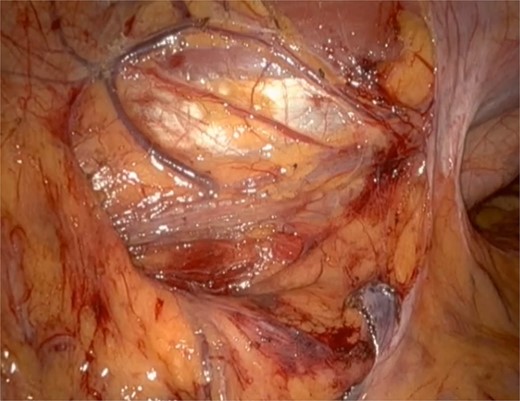

He underwent a robotic excision of his paraganglioma in a right lateral position, using a transperitoneal approach with three robotic ports and one assistant port in the midline. The left colon was mobilized medially, exposing the tumour. After identifying the ureter and gonads, the tumour was dissected freely using a vessel sealer, before removing it in a specimen bag. Operation was uneventful (Figs 3 and 4).

Post tumour removal showed clean base with no active bleeding. No evidence of tissue invasion into peripheral structures.